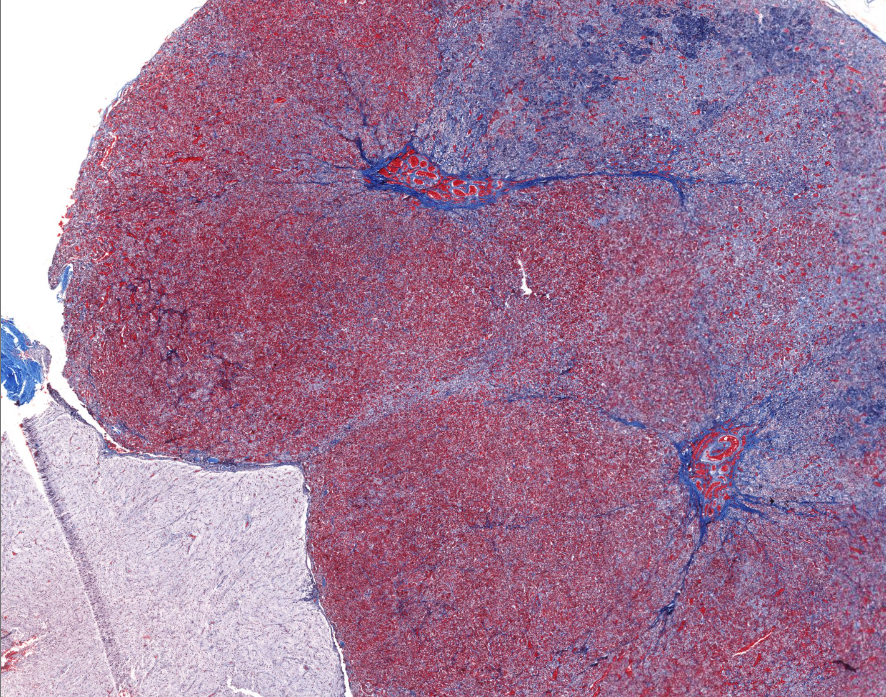

spleen

solid organ

“white” pulp

made up of lymphocytes

lots of basophils

“red” pulp

filters and degrades RBCs